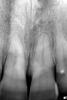

Елка Опубликовано 10 октября, 2009 Поделиться Опубликовано 10 октября, 2009 Добрый день!Помогите пожалуйста, что с моим зубом. На снимке левый передний. Врач после чистки канала с казала, что сломан корень зуба и его нужно удалять. Зуб болит, имеется свишь между передними зубами, но опухоль уже спала. Зуб немного подвижный. Естественно мне очень хочется сохранить зуб. Я сомневаюсь по поводу перелома, т.к. на первом снимке то, что мне показывают как перелом видно на правом зубе. А на втором на левом. В случае, если это дествительно перелом, есть ли шанс спасти зуб? Ссылка на комментарий

zybnaya feya Опубликовано 10 октября, 2009 Поделиться Опубликовано 10 октября, 2009 какая разница во времени между снимками?и почему перелом приключился? травмы были? по снимку - похоже на перелом.если это поперечный перелом корня - есть шанс убрать зуб и поставить имплант. пока есть кость. и красиво с десной получится.мож, снимок еще сделать в канале с контрастом? или КТ?+1 на втором снимке видна линия перелома. И изменения уже в косной ткани. Зуб на удаление Ссылка на комментарий

zybnaya feya Опубликовано 10 октября, 2009 Поделиться Опубликовано 10 октября, 2009 Разница во времени неделя. Первый снимок до вскрытия канала. травма была пол года назад -удар восковым мелком. Меня смущает, что на первом снимке ничего не видно....Ну конечно на первом снимке "ничего не видно" вы же его перевернули слева направо . Посмотрите что 2-ка(на ней беленькая точечка,как маркер оказался на первом снимке у вас с левой стороны,а на втором с правой). Там линия перелома видна на обоих снимках(только на первом снимке смотреть надо на тот зуб который правее) http://i011.radikal.ru/0910/7b/6e2edc533be3.jpghttp://s51.radikal.ru/i132/0910/4e/6f2cd2a7d85a.jpg Ссылка на комментарий

zybnaya feya Опубликовано 10 октября, 2009 Поделиться Опубликовано 10 октября, 2009 (изменено) фей у автора не догон что ты там хотела показать своими "кружочками"она может в школе не училась-физики не знаетто такое стереоизомеры тоже не знаетвообще что изомерия и симметрия не знаетпро фокус с зеркальным изображением вообще молчуу неё может и зеркала дома нет.суть не в этомтут я как погляжу оба резца "переломанные" ну я еше не знаю как обьяснить по простому,про изомерию и симметрию я уж и не стала ничего говорить,если уже и наглядно обвела и не понятно,я не в силах помочь)))) Ну в одном из резцов перелом есть это точно,иначе резорбции не было бы в области линии перелома. (с номером зуба я уже сама затрудняюсь,ибо снимки перевернуты). Просто пациенту не хочеться видеть проблему ДО вмешательства доктора,а хочеться чтоб тут все сказали,что теперлом появился ПОСЛЕ лечения. А ЭТО НЕ ТАК Изменено 10 октября, 2009 пользователем zybnaya feya Ссылка на комментарий

Чиффа Опубликовано 10 октября, 2009 Поделиться Опубликовано 10 октября, 2009 Ёлка! снимки не должны быть идеально идентичны! их же с помощью человека делают: чуть смести трубку или датчик визиографа, и вуаля! и корни разной длины, и смотрят в разные стороны....по снимкам перелом на одном и том же зубе и на первом снимке и на втором. о его перспективах Вам уже написали. Ссылка на комментарий